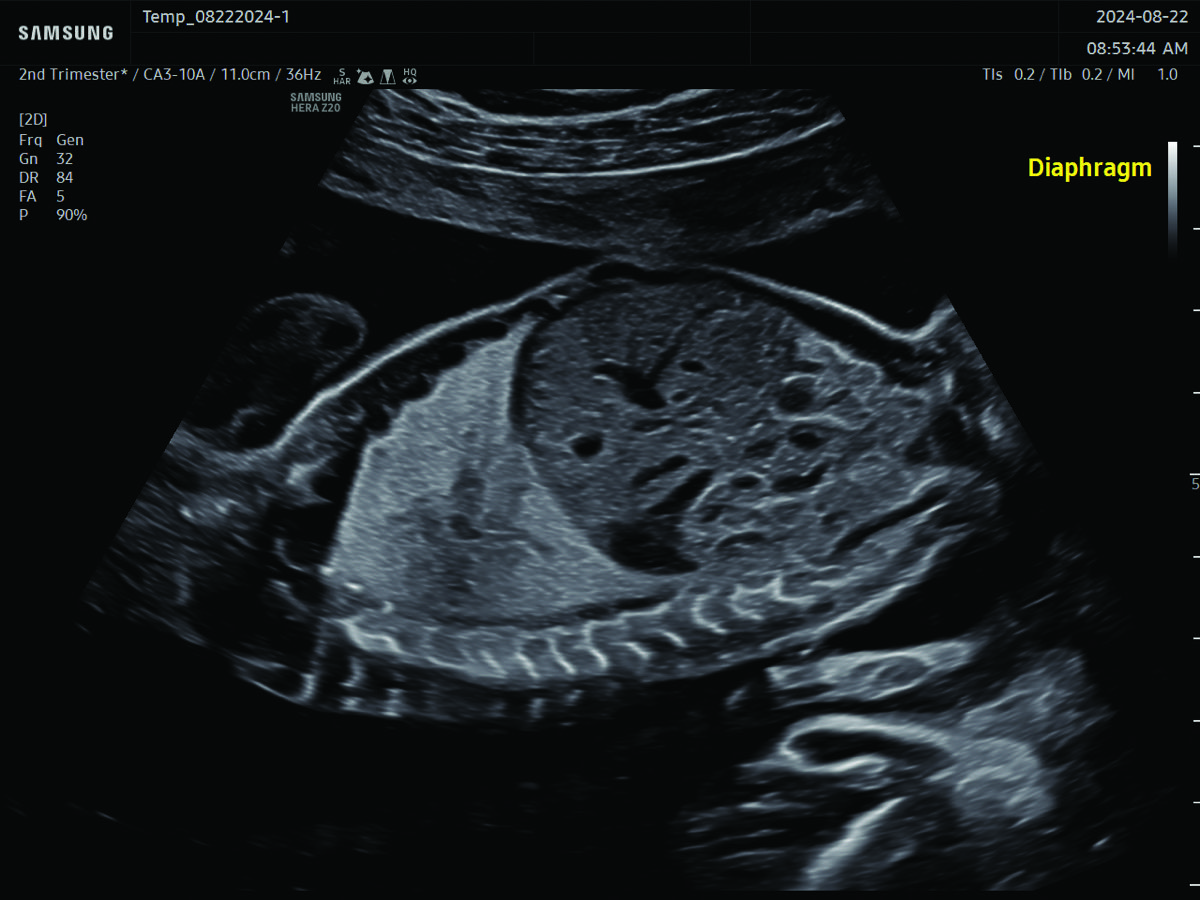

Comprehensive, advanced and expert MFM care for high-risk pregnancies

- Fetal anomalies